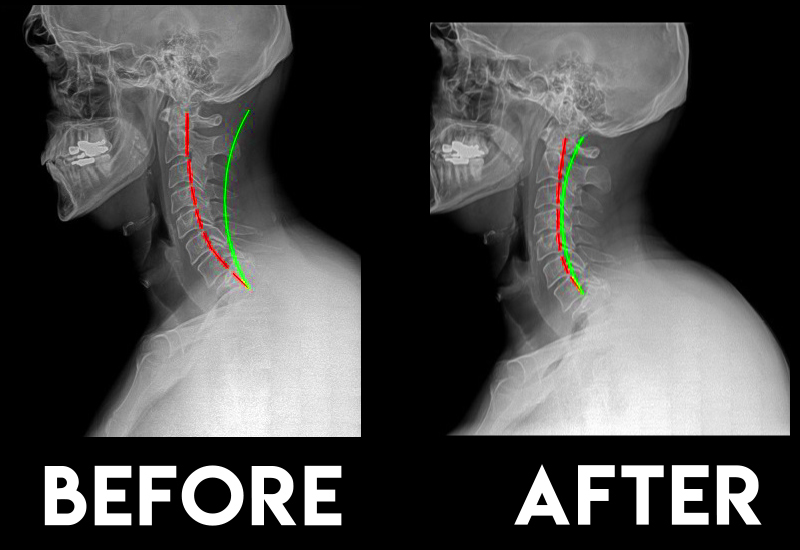

- Insight Scans (X-Rays)